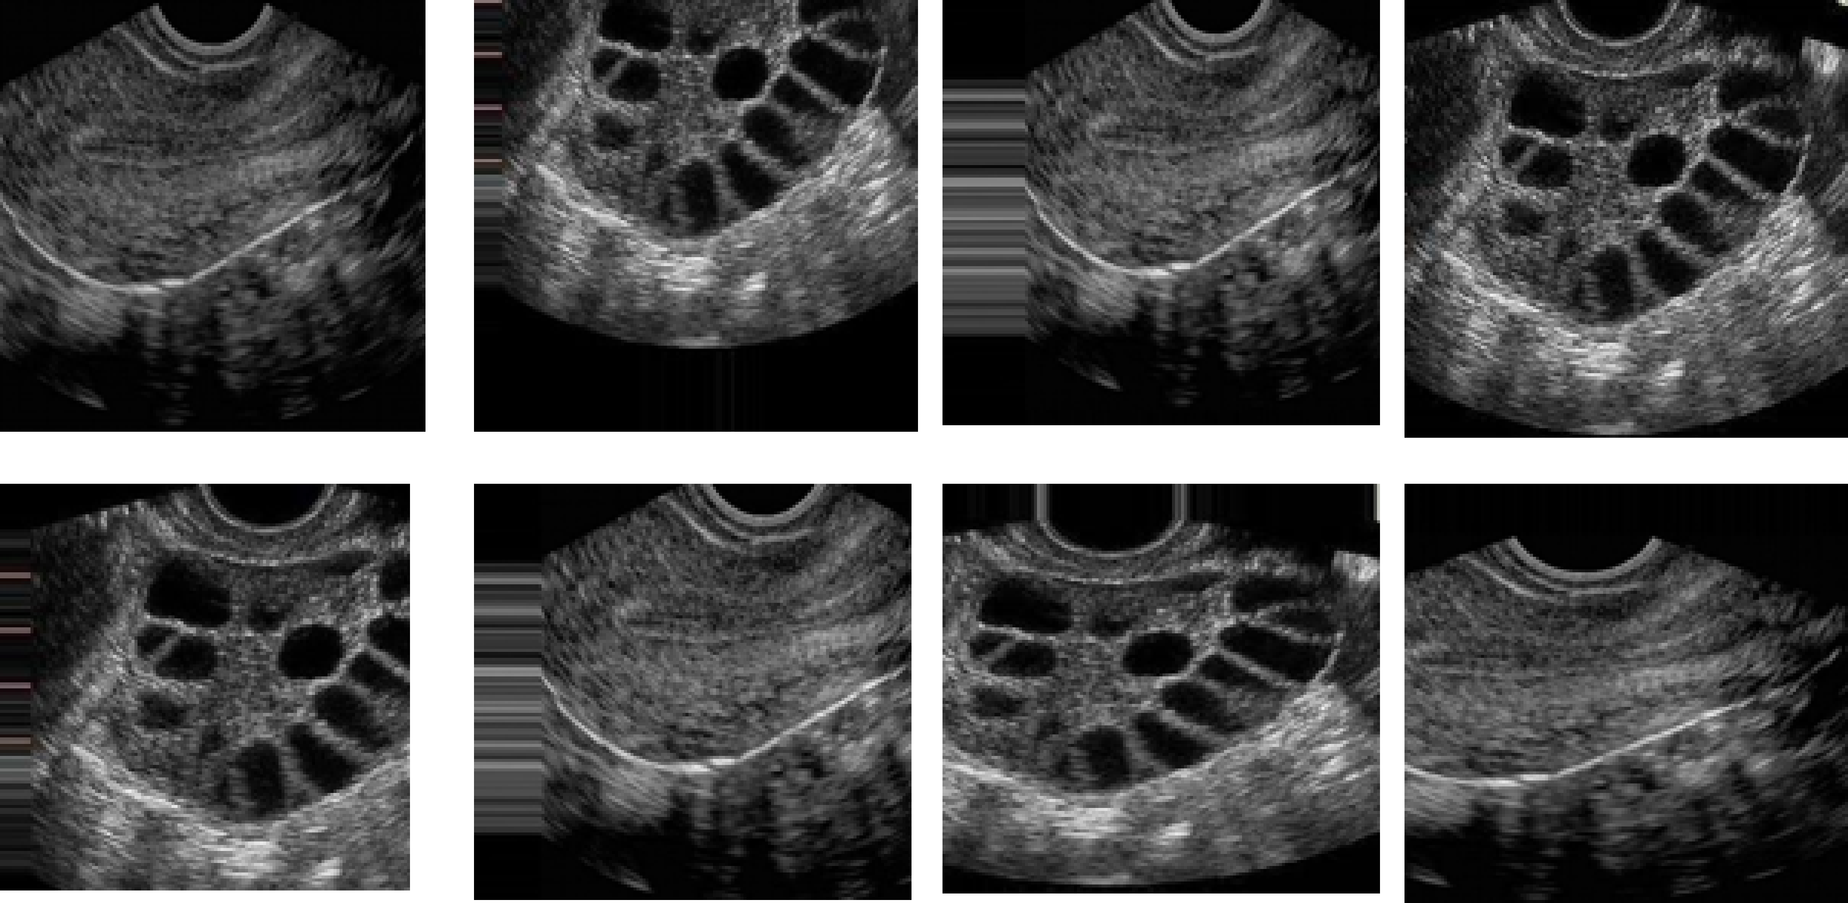

Sample PCOS Ultrasound Dataset Images.

From: Feature fusion context attention gate UNet for detection of polycystic ovary syndrome